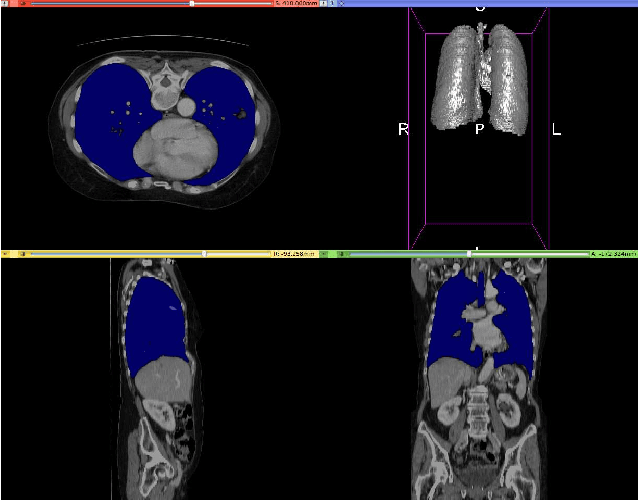

Abstract:Fully-convolutional neural networks have achieved superior performance in a variety of image segmentation tasks. However, their training requires laborious manual annotation of large datasets, as well as acceleration by parallel processors with high-bandwidth memory, such as GPUs. We show that simple models can achieve competitive accuracy for organ segmentation on CT images when trained with extensive data augmentation, which leverages existing graphics hardware to quickly apply geometric and photometric transformations to 3D image data. On 3 mm^3 CT volumes, our GPU implementation is 2.6-8X faster than a widely-used CPU version, including communication overhead. We also show how to automatically generate training labels using rudimentary morphological operations, which are efficiently computed by 3D Fourier transforms. We combined fully-automatic labels for the lungs and bone with semi-automatic ones for the liver, kidneys and bladder, to create a dataset of 130 labeled CT scans. To achieve the best results from data augmentation, our model uses the intersection-over-union (IOU) loss function, a close relative of the Dice loss. We discuss its mathematical properties and explain why it outperforms the usual weighted cross-entropy loss for unbalanced segmentation tasks. We conclude that there is no unique IOU loss function, as the naive one belongs to a broad family of functions with the same essential properties. When combining data augmentation with the IOU loss, our model achieves a Dice score of 78-92% for each organ. The trained model, code and dataset will be made publicly available, to further medical imaging research.